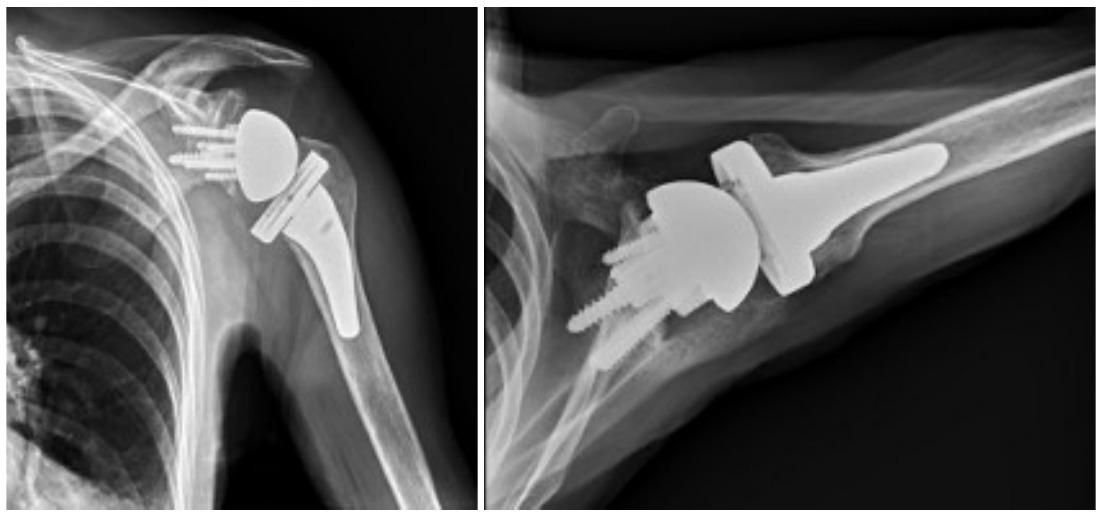

Case one is a 58-year-old male who is an avid golfer with long standing right shoulder pain. Surgical history includes previous Bristow procedure 30 years prior. Current Subjective Shoulder Value (SSV) is 30% and pain is 8/10 at baseline. Active range of motion was 110° of forward flexion, -10° of external rotation and interna rotation to the lateral buttock. Radiographs (Figure 1) and computed topography (CT) scan (Figure 2) show retained implants with loss of joint space, glenoid retroversion, and significant posterior humeral head subluxation. The patient had failed conservative management and was indicated for arthroplasty. Due to significant posterior bone loss and retroversion, an augmented anatomic component was selected for this patient. Radiographs at one year show a well seated glenoid component with restoration of the joint line and a centered humeral head (Figure 3). At five years, SSV had improved to 95% with excellent clinical motion (Figure 4).